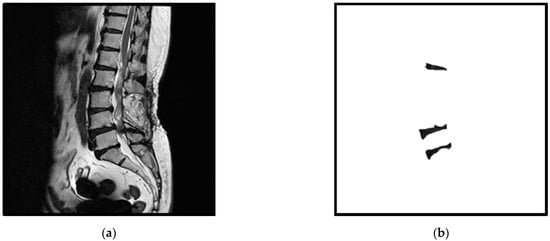

In this study, we first used the MultiResUNet model to segment three specific intervertebral discs. The MultiResUNet model can easily implement the training work of segmentation of these three specific intervertebral discs; however, segmentation errors often occur during the testing phase. These errors include the segmentation of redundant intervertebral discs or the segmentation of the wrong (non-specific) intervertebral discs. Figure 2 shows an example of a segmentation error, where an extra intervertebral disc is segmented. In order to solve these segmentation error problems, this study proposes a two-stage method based on the MultiResUNet model. For more technical description of MultiResUNet, please refer to the Appendix A.

Figure 2.

An example of a segmentation error: (a) the standard masks of the three intervertebral discs; (b) the segmentation error of a redundant intervertebral disc using the MultiResUNet model.